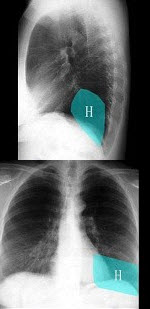

270、单项选择题

如图,在正常胸部X线影像图像上,该英文字母所代表的肺段为()

A.内基底段

B.前基底段

C.外基底段

D.后基底段

E.背段

点击查看答案